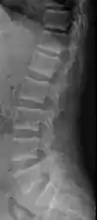

X-ray of a subtle "rugger jersey spine" due to sclerotic bands adjacent to the vertebral endplates.[18]

CT scan of the same case.[18]